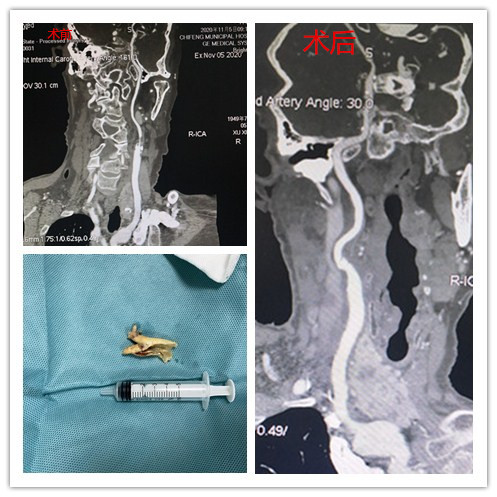

患者二:男性,57岁,主因“发现右侧颈内动脉重度狭窄1月余”入院,术前检查CTA检查提示右侧颈总动脉近分叉处及分叉后颈内动脉、颈外动脉重度狭窄。

▲图中黄色箭头示术前狭窄处,术后复查消失